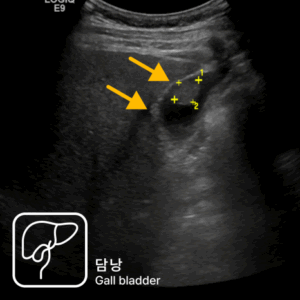

가스 차는 증상과 경미한 혈변으로 발견된 직장암 사례설사와 혈변, 항문 통증으로 내원했다가 직장암을 진단받은 40대 남성 사례심한 변비로 내원하여 상행결장암을 진단받은 80대 남성 사례속쓰림으로 내원했다가 복부초음파로 조기 담낭암을 발견한 사례명치 통증과 소화불량으로 내원했다가 췌장암 3기가 진단된 사례무증상 검진 중 갑상선초음파로 발견된 조기 갑상선 유두암 사례유방 통증으로 내원했다가 유방초음파로 조기 진단된 침윤성 유방암 사례명치 통증으로 내원했다가 진행성 위암을 발견한 60대 여성 사례속쓰림으로 내원했다가 signet ring cell type 위암을 조기 발견한 60대 여성 사례소화불량으로 내원했다가 작은 조기 위선암을 발견한 50대 여성 사례변비로 내원했다가 침윤성 궤양 형태의 위암을 발견한 70대 여성 사례소화불량으로 내원했다가 진행성 위암을 발견한 60대 여성 사례경미한 속쓰림으로 방문했다가 조기 위선암을 발견한 60대 여성 사례가스 차는 증상과 경미한 혈변으로 발견된 직장암 사례설사와 혈변, 항문 통증으로 내원했다가 직장암을 진단받은 40대 남성 사례심한 변비로 내원하여 상행결장암을 진단받은 80대 남성 사례속쓰림으로 내원했다가 복부초음파로 조기 담낭암을 발견한 사례명치 통증과 소화불량으로 내원했다가 췌장암 3기가 진단된 사례무증상 검진 중 갑상선초음파로 발견된 조기 갑상선 유두암 사례유방 통증으로 내원했다가 유방초음파로 조기 진단된 침윤성 유방암 사례명치 통증으로 내원했다가 진행성 위암을 발견한 60대 여성 사례속쓰림으로 내원했다가 signet ring cell type 위암을 조기 발견한 60대 여성 사례소화불량으로 내원했다가 작은 조기 위선암을 발견한 50대 여성 사례변비로 내원했다가 침윤성 궤양 형태의 위암을 발견한 70대 여성 사례소화불량으로 내원했다가 진행성 위암을 발견한 60대 여성 사례경미한 속쓰림으로 방문했다가 조기 위선암을 발견한 60대 여성 사례

30년 경력 의료진의 판독,

세란의 초음파 클리닉

내과·영상의학과 전문의가

직접 검사부터 판독까지

30년 경력의 영상의학과

의료진이 함께하는 신뢰도 높은 진단

당일 검사, 당일 결과 확인 가능합니다.